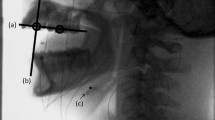

Surface EMGs were recorded from the bilateral masseter muscles, the bilateral anterior belly of the digastric muscles, and the genioglossus muscle of the habitual chewing side. The sEMG recordings of the masseter muscles and anterior belly of the digastric muscle were obtained for 12 subjects, and the sEMG of genioglossus muscle was obtained for first 5 consecutive recruited subjects. The habitual chewing side was determined by placing half a piece of cotton roll on the center of the tongue and observing the direction to which the cotton roll was moved during the first chewing cycle [18, 19]. Silver/silver chloride surface disc electrodes (bioelectrode Futami Emu Ih Industries Co., Ltd.) with a diameter of 10-mm were attached to the skin over the center of the masseter muscle and the anterior belly of the digastric muscle. The location of the electrode was determined by palpation of the muscles during tasks involving clenching for the masseter muscles and lifting up the tongue for the anterior belly of the digastric muscle, respectively. The distance between the center of the electrodes was set at 10-mm and the bipolar sEMG signals were derived and recorded. Regarding recording of the anterior belly of the digastric muscle activity, activities of the suprahyoid muscles, such as the geniohyoid and mylohyoid muscles, in the submental region were combined, so that activity of the anterior belly of the digastric muscle was recorded as part of the suprahyoid musculature activities [20, 21]. This compound was also considered with recording of the genioglossus muscle activity. The ground electrode was attached to the back of the neck. The muscle activity of the genioglossus was bipolar derived using custom-made silver ball electrodes (2-mm diameter), which were incorporated in the lingual flange of the experimental splint using a self-curing resin (UNIFAST II-clear, GC). The electrodes were positioned at the border of the lingual flange between the distal right lateral incisor and canine teeth, with a 7-mm distance between electrodes (Fig. 1). A lead wire was passed through the lower interproximal embrasure among the canine tooth and the first and second premolars. Additionally, to enhance the retention of the experimental splint, wire clasps with a diameter of 0.9 mm were attached to the last molars (Fig. 1). The method used to record the activity of the genioglossus muscle was similar to that used in previous studies monitoring the genioglossus activity during respiration [22, 23]. Before the recording sessions, the numbers of masticatory cycles with and without the splint were measured.

Analyzed parameters. Ms: onset of activity of the masseter muscle, Ds: onset of activity of the anterior belly of the digastric muscle, Gs: onset of activity of the genioglossus muscle, Me: offset of the masseter activity, De: offset of the digastric activity, Ge: offset of the genioglossus activity, Se: offset of swallowing, Mat: duration of the masseter activity, Dat: duration of the digastric activity, Gat: duration of the genioglossus activity, Dst: initial activation timepoint of the anterior belly of the digastric, Gst: initial activation timepoint of the genioglossus, GSet: total duration of swallowing